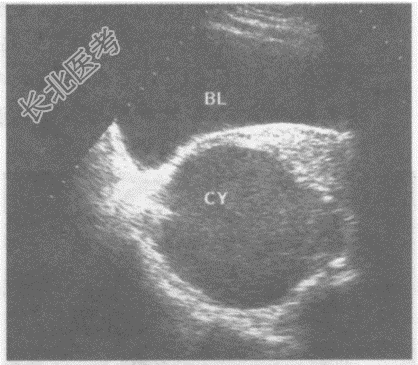

- 单项选择题临床资料:女性, 28岁,常规体检。

超声综合描述: 子宫形态、大小正常,肌层回声均匀。子宫右后方可见不规则无回声区, 边界清晰,囊壁厚, 内透声不清亮,可见点状中强回声。

其超声提示: A、右卵巢囊肿蒂扭转

B、盆腔脓肿

C、右卵巢巧克力囊肿

D、右输卵管积液

E、卵巢癌